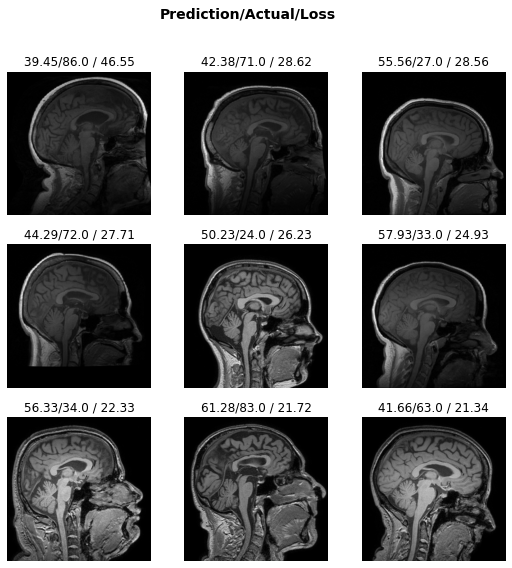

learn.load('brainage-weights');interp = Interpretation.from_learner(learn)interp.plot_top_losses(k=9, anatomical_plane=2)